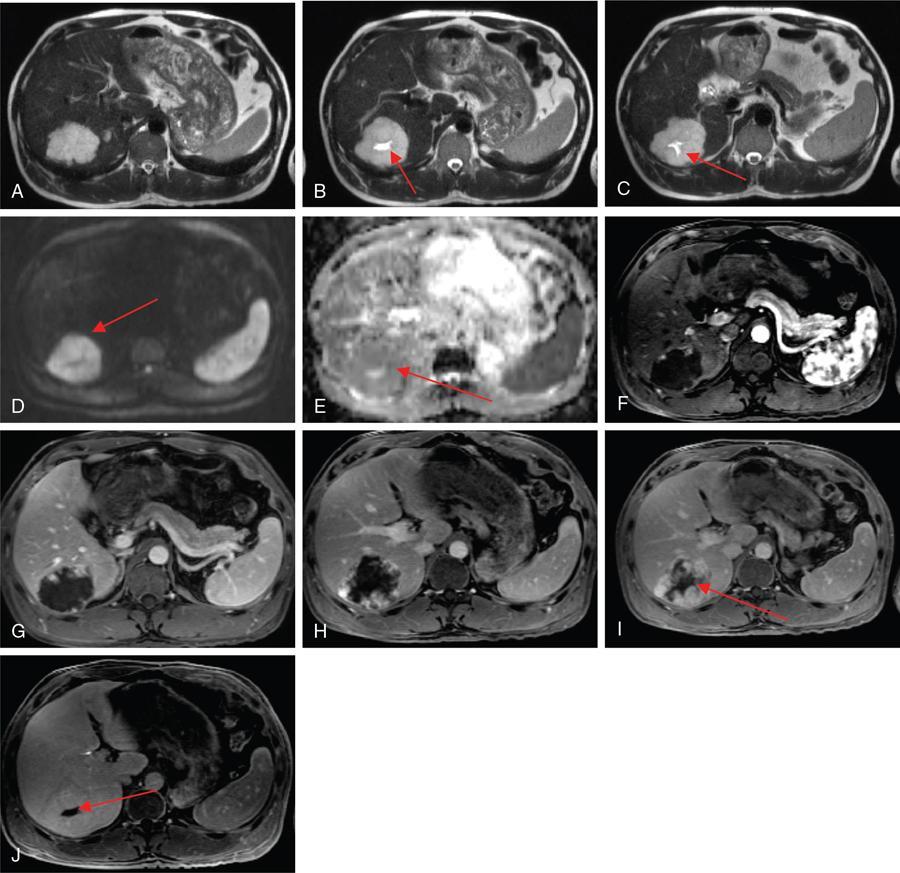

Ritu K. Kashikar, Shrinivas B. Desai, Pooja Punjani Vyas, Nilesh Doctor, Vivek Shetty Owing to advances in technology, focal liver lesions (FLLs) are increasingly encountered. Imaging particularly computed tomography (CT) and magnetic resonance imaging (MRI) play a vital role in diagnosis and characterization of FLL, thus avoiding unnecessary biopsies and interventions. Multiphase CT accurately diagnosis most liver lesions. Better soft tissue contrast and lack of ionizing radiation makes MRI a preferred modality in diagnosing FLLs. MRI with or without contrast for characterization of liver lesions regardless of preexisting liver disease has been assigned the highest rating as per American College of Radiology Appropriateness Criteria (Table 9.11.1). Solid lesions of epithelial origin Solid lesions of nonepithelial origin Pitfalls Cystic liver lesion Developmental cyst Infective cyst Miscellaneous Tmours of hepatocellular origin Tumours of nonepithelial origin Malignant cystic lesion Hepatic metastasis Ultrasound is often the initial modality for diagnosis and also the incidental detection of FLLs. Limitations to USG include the detection of small lesions less than 2 cm in size, particularly in patients who are cirrhotic or undergoing chemotherapy. Characterization of FLLs, involvement of crucial structures such as blood vessels, local staging and decisions such as operability are also not accurate with ultrasound alone and require confirmation with CT/MRI. The liver typically images in supine and left lateral positions. A curvilinear transducer with a frequency of 1.5 Hz is used. The subcostal diagonal, subcostal longitudinal or sagittal and transverse right intercostal lateral views are used. Right lobe of liver is imaged through an intercostal approach when the patient is taking deep inspiration. Subcostal view is used to image the three hepatic veins in one view. Transverse, longitudinal and oblique views of the liver are taken to image all the segments of liver. Colour and power Doppler have increased sensitivity for FLL detection, but sensitivity is still inferior to contrast-enhanced CT and MRI. The introduction of microbubble contrast agents (CAs) and the development of contrast-specific techniques have opened new perspectives in ultrasound of the liver. The technique is based on a new class of intravascular microbubble agents which contain perfluoro gases instead of air. This when combined with scanning modes sensitive to harmonic responses of microbubbles enable tissue signal suppression. The advent of the multislice technique and isotropic voxel have improved the spatial resolution of CT, allowing the recognition of small FLLs in difficult areas. Multislice CT has a sensitivity and specificity in the diagnosis of malignant FLLs of 63% and 64%, and 92 and 97%, respectively. Contrast media administration with dose based on the patient’s weight (approximately 600 mg iodine/kg of bodyweight), an iodine content of 350–400 mg/mL and a high injection rate of 4–5 mL/s are imperative to attain good contrast enhancement. Region of interest in the abdominal aorta and a threshold of 100 HU allows correct timing for threshold. A delay of approximately 18 s after the threshold provides the first arterial phase, allowing detection of hypervascular FLLs such as hepatocellular carcinoma (HCC). The late arterial phase is obtained approximately 10 s after the early arterial phase and shows progressive enhancement of hypervascular lesions, improving detection rate, while the optimal hepatic enhancement in the portal phase is reached approximately 50–60 s after the threshold. Portal venous thrombi are also best detected in this phase. The venous phase aids in the detection of washout, hepatic venous thrombosis. Delayed phase is often required in lesions such as cholangiocarcinoma and haemangioma, which show progressive enhancement (Table 9.11.2, Fig. 9.11.1). Delayed phase images are required for tumours such as cholangiocarcinoma and large haemangiomas, which reveal delayed enhancement. As mentioned previously, MRI is the modality of choice in diagnosis of FLLs. Most FLLs appear hyperintense on T2W1 images with varying intensity depending upon the water content and flow dynamics. FLLs are typically hypointense on T1W1 images with the exception of fat containing, haemorrhagic lesions and those containing chelates of metals like regenerating/dysplastic nodules. In- and opposed-phase images help in detection of intralesional fat. Diffusion-weighted images are beneficial particularly in noncirrhotic population and best suited in detection of metastasis. Postcontrast images obtained with extracellular agents are parallel to those obtained with CT (Fig. 9.11.2). The pre- and postcontrast MRI protocol is mentioned in Table 9.11.3. T2-weighted single-shot fast spin-echo (SE) T1-weighted in- and opposed-phase GRE Dynamic 3D T1-weighted FS spoiled GRE (in hepatic arterial, portal venous and equilibrium phases) There are two main categories of CAs used in liver imaging – the extracellular and the hepatocyte-specific (Fig. 9.11.3). Extracellular agents are more widely used and provide information similar to contrast-enhanced CT study. The advantage of the other category of CAs, that is, hepatocyte-specific agents, is the ability to provide this extracellular information with added benefit of delayed phase information. Tumours of hepatocellular origin with functioning hepatocytes take up and biliary excretion with take up and retain these agents appearing isointense to background liver. Lesions without functioning hepatocytes fail to retain contrast and hence appear hypointense to background liver on delayed phase. This allows better detection and characterization of focal liver lesion particularly those lesser than 2 cm (Table 9.11.4). Haemangioma is the most common benign hepatic tumour. The incidence in general population varies from 1% to 20%. Females have a higher preponderance with variable female to male ratios of 2:1 to 5:1. Imaging in particular MRI has high reliability in diagnosing classic haemangioma. The sensitivity and specificity of MRI is greater than 90% in diagnosis. The aetiology of haemangioma is unknown. Since haemangiomas are known to run in families, a genetic origin has been implicated, while other mesenchymal tumours are thought to be congenital. Most patients are asymptomatic and often the lesion is discovered as an incidental finding. Pain in the right upper abdomen is the most common complaint; others include loss of appetite, nausea, vomiting and abdominal discomfort. Symptoms are usually seen in large haemangiomas or those with complications. Liver function tests and tumour markers like AFP and CA19.9 are within normal limits. Blood-filled cavities of varying sizes lined by flat endothelial cells and supported by fibrous connective tissue are seen on histology. Three histological subtypes have been described: the capillary haemangioma, the cavernous haemangioma and the sclerosing haemangioma. The imaging features of a haemangioma depend on its size; typical haemangiomas are mostly less than 3 cm in diameter. Haemangiomas are hyperechogenic, homogeneous lesion presenting a posterior acoustic enhancement (Fig. 9.11.3). The hyperechogenicity of haemangiomas is related to the interfaces between vascular spaces, fibrous stroma and the slow blood flow. Typically, haemangiomas have slow flow and hence do not show vascularity on colour or power Doppler. The sensitivity and specificity of ultrasound in differentiating haemangioma from other malignant lesions are high, with values of approximately 94.1% and 80%, respectively, for lesions less than 3 cm in diameter. Unlike HCC, no flow is seen on colour Doppler. A peripheral echogenic rim around hypoechoic lesions can suggest haemangioma. On the contrary, perilesional hypoechoic rim called the target sign is seen in lesions such as metastasis (Table 9.11.5). Adenomas can be distinguished on the basis of the absence of posterior acoustic enhancement and characteristic pattern of peripheral vascularity seen in adenoma. Another differential diagnosis to be considered is focal nodular hyperplasia (FNH), which has the characteristic ‘spoke-wheel sign’. Contrast-enhanced ultrasound (CEUS) improves specificity for the diagnosis of haemangioma. The vascularity pattern with contrast-enhanced USG is similar to that seen with CT. The typical hemangioma (HH) shows peripheral nodular enhancement in the arterial phase with complete (but sometimes incomplete) centripetal filling in the portal venous and late phases. This particular pattern of enhancement helps in differentiating haemangiomas from other lesions like adenomas, FNH, HCC or metastasis. This characteristic enhancement pattern has a sensitivity of 98% for histologically proven HH. One should be aware that an HH can rarely have a centrifugal enhancement. Computed tomographic (CT) findings consist of a hypoattenuating lesion on nonenhanced images. Haemangiomas show peripheral discontinuous nodular enhancement on arterial phase of dynamic contrast-enhanced CT. The density of the nodules is equivalent to that of the aorta. Centripetal filling with is seen on venous phase, which progresses to uniform enhancement. The enhancement persists on delayed phase (Fig. 9.11.4). Washout of contrast on delayed phase is not seen in haemangioma and if seen, alternate diagnosis must be considered. This classical pattern of enhancement cannot be highlighted in very small lesions of less than 5 mm, which can be difficult to characterize. In patients with severe fatty infiltration of the liver, HH can appear hyperdense relative to the adjacent liver parenchyma on nonenhanced scan. Haemangiomas are hyperintense on T2-weighted images, which is identical to that of cerebrospinal fluid. T2 hyperintense signal is classically described as ‘light bulb bright’. Malignant lesions of the liver do not appear as bright on T2W1 images. They appear hypointense to adjacent liver on T1-weighted images. Long relaxation T2W1 images further improve accuracy in diagnosis of haemangiomas and help in differentiation from metastasis. Haemangiomas, unlike other liver lesions retain hyperintense signal on long relaxation T2W1 images. A threshold of 112 ms has 92% accuracy, 96% sensitivity and 87% specificity for differentiating haemangiomas from metastasis. On gadolinium administration, the enhancement pattern is similar to that seen with iodinated contrast on CT. Classic enhancement pattern in combination with characteristic T2 appearance are diagnostic for haemangioma (Fig. 9.11.5). Certain pitfalls exist in diagnosing haemangiomas using gadoxetate disodium. Due to the lack of hepatocytes, haemangiomas appear hypointense to the background liver on delayed hepatocyte phase and mimicking malignant process (Table 9.11.6). Lesions shown peripheral nodular arterial enhancement (Table 9.11.7): On fluorodeoxyglucose-positron emission tomography (FDG-PET)/CT, most hepatic haemangiomas appear low-attenuation lesions with FDG avidity equal to background liver parenchyma and are easily determined to be benign. However, a small percentage of haemangiomas may be FDG-avid. If an FDG-avid hepatic lesion demonstrates the characteristic enhancement pattern, this is consistent with an FDG-avid haemangioma. Technetium-99m pertechnetate-labelled red blood cell scintigraphy has high specificity in the diagnosis of haemangiomas. In this technique, there is decreased activity in haemangiomas on early images and increased activity on delayed blood pool images. Therefore, radionuclide scintigraphy has a sensitivity of 78% and an accuracy of 80% and may be a valuable tool when the diagnosis cannot be achieved with other imaging modalities. Large haemangiomas are often heterogeneous with internal clefts and septae. They are termed as giant haemangiomas when they exceed 4 cm in diameter. Discrepancies are there in definition with some authors defining giant haemangiomas as lesions greater than 6 cm or 12 cm in diameter. These may cause symptoms of abdominal pain and distension. These haemangiomas demonstrate changes such as haemorrhage, thrombosis, extensive hyalinization, liquefaction and fibrosis. The central cleft-like area may be due to cystic degeneration or liquefaction. On USG, they reveal heterogeneous echotexture. They are hypoattenuating and heterogeneous on nonenhanced CT with central areas of low attenuation. After intravenous administration of contrast material, the typical early, peripheral and globular enhancement is observed. These may show irregular or ‘flame-shaped’ discontinuous peripheral enhancement as opposed to typical nodular enhancement pattern seen in smaller haemangiomas. Although centripetal pattern of enhancement is seen during the venous and delayed phases, the filling-in incomplete. Central scars are defined in this subset of haemangiomas (Fig. 9.11.6). At MRI, T2-weighted images show a markedly hyperintense cleft-like area and some hypointense internal septa within a hyperintense mass. On delayed phase, incomplete filling and central scar are seen similar to CT (Fig. 9.11.7). Complications include intratumoural haemorrhage, inflammatory changes or consumptive coagulopathy (Kasabach–Merritt syndrome). These may warrant management such as arterial embolization or resection. This pattern is seen 16% of all haemangiomas, and is seen more often in small haemangiomas (42% of haemangiomas) <1 cm in diameter. CT and MRI show immediate homogeneous enhancement at arterial phase CT or contrast-enhanced MRI. The size of the blood spaces is the reason for difference in enhancement pattern. Smaller the lesion, smaller the size of blood spaces and faster the rate of spread of contrast material. These lesions usually show perilesional halo of hyperenhancement on the late arterial phase, which is believed to be due to arteriovenous shunting. Rapid arterial enhancement makes these haemangiomas difficult to distinguish from hypervascular metastasis (Table 9.11.8). However, washout of contrast is seen from haemangiomas on delayed phase (Fig. 9.11.8). Hepatic haemangiomas rarely demonstrate calcifications, while haemangiomas in other locations frequently demonstrate phleboliths. Calcified haemangiomas are mostly found incidentally. Calcifications may occur in the marginal or central portion of the lesion and consists of multiple spotty calcifications, which correspond to phleboliths. However, large, organized calcifications are also possible. Some calcified haemangiomas may demonstrate poor enhancement. Hyalinized hepatic haemangiomas are rare. It has been suggested that hyalinization represents an end stage of haemangioma evolution. These haemangiomas are usually asymptomatic. The radiological features of a haemangioma are completely altered ones hyalinization occurs; hence biopsy is often mandatory for diagnosis. Hyalinized haemangiomas show only slight high signal intensity on T2W1 images. There is lack of early enhancement on dynamic contrast-enhanced images (Fig. 9.11.9). Fluid–fluid levels within haemangiomas are very rare. Fluid–fluid levels are seen both with CT and MRI with inferior layer representing the red blood cells and superior layer unclotted serous blood. Dependent hyperdensity/T1 hyperintensities can be seen corresponding with dependent haemorrhage. Pedunculated haemangiomas are very rare. They can be asymptomatic or complicated by subacute torsion and infarction. Typical enhancement pattern and signal on T1 and T2W1 images are clues to the diagnosis. Capsular retraction is usually associated with malignant tumours such as cholangiocarcinoma, epithelioid haemangioendothelioma or metastases. Rarely, it has been seen in haemangiomas. A possible mechanism could be fibrous degeneration. Multiple haemangiomas are seen in 10% of cases and usually show classical imaging features. Fatty infiltration of liver may alter the imaging appearances of lesions. Haemangiomas appear slightly hyperechoic, isoechoic or hypoechoic relative to the fatty liver. At nonenhanced CT, the lesion may be hyperattenuating relative to the liver. Contrast-enhanced CT shows peripheral enhancement and delayed filling, an appearance similar to that of a haemangioma in a normal liver. Haemangiomas are less common in setting of cirrhosis and may be difficult to diagnose due to sclerosis. Complications are seen in 4.5%–19.7% and often seen in large lesions such as inflammation, coagulation within can lead to systemic disorders, haemorrhage would lead to haemoperitoneum, volvulus and adjacent organ compression. Irrespective of the size, treatment is indicated only for haemangiomas with significant symptoms, those developing complications, or when there is an inability to exclude malignancy. Attempt should be made to exclude other causes of the patient’s symptoms. The term focal nodular hyperplasia (FNH) was introduced in 1958 by Edmondson. In 1995, the International Working Party classified FNH with other regenerative lesions, and not a neoplastic lesion. It is defined as a nodule consisting of normal appearing hepatocytes occurring in a histologically normal liver. It is the second most common tumour of the liver after haemangioma with a reported prevalence of 0.9%. The lesion is more commonly seen in females with female to male ratio of 8:1. Multiplicity is seen in 20% of patients. The combination of multiple FNH lesions and haemangiomas is considered to be multiple FNH syndrome. Vascular malformation and vascular injury have been suggested as the underlying mechanism. An association with steroids has been denied more recently. FNH has been classified as classic and nonclassic varieties. These have been discussed in Table 9.11.9. Classic FNH is characterized by abnormal nodular architecture, malformed vessels and cholangiolar proliferation. Nonclassic FNH lesions lack one of the following classic features – nodular abnormal architecture or malformed vessels – but always show bile ductular proliferation. Classic FNH on gross appearance shows lobulated contours with multiple nodules surrounded by fibrous septae originating from a central scar, which contains a vascular malformation. On histopathology, nodular hyperplastic parenchyma is seen in classic FNH. Circular or short fibrous septae surround these nodules completely or incompletely. Thickening of the hepatic plates is seen. Fibrous connective tissue, cholangiolar proliferation with surrounding inflammatory infiltrates and malformed arteries, capillaries, vascular channels of undetermined type and veins are seen in the central scar. The arterial blood in FNH shows centrifugal distribution from anomalous central arteries. Fatty infiltration is seen in approximately 50% of lesions, while signs of hepatic steatosis are seen in approximately 20% of cases with classic FNH. Variable amounts of Kupffer cells are seen in both classic and nonclassic variants. Nonclassic FNH is heterogeneous and on gross appearance resembles adenomas in most cases, with vaguely lobulated contours and lack of a macroscopic central scar. The histology varies with subtypes. Subtypes of nonclassic FNH include telangiectatic type, mixed hyperplastic and adenomatous forms and FNH with cytologic atypia. The histological features of these are described in Table 9.11.10. At US, typical FNH is often not well visualized. The lesions may be slightly hypoechoic, isoechoic or slightly hyperechoic. The compressed liver tissue form a hypoechoic halo around the lesion, which appears more prominent in patients with fatty infiltration. A prominent central scar may improve the conspicuity of the lesions. Use of colour and power Doppler US shows vascularity in suspected FNH. On contrast-enhanced USG, FNH is hyperenhancing in the arterial and portal venous phases in more than 90% of cases. The arterial enhancement patterns include central (60%–70% of cases) or eccentric (<20% of cases) with centrifugal filling, but sometimes are homogeneous. Multiphase CT is an excellent modality for detection and characterization of FNH. These lesions classically show a lobulated contour. At unenhanced CT, the lesions are either hypoattenuating or isoattenuating to the surrounding liver. In the arterial phase, the lesions show homogeneous intense enhancement except the central scar and fibrous septa. In the portal and later phases, the lesions become more isoattenuating with the surrounding liver. The central scar reveals enhancement on delayed phase (Fig. 9.11.10). This feature helps distinguish from other lesions with central scar-like fibrolamellar carcinoma. A vascular malformation can be seen in the central scar in some cases (Fig. 9.11.11). There may be enlarged hepatic veins in the vicinity of the mass. FNH do not have portal venous drainage. The drainage is essentially into hepatic venules, hence the enlarged adjacent veins. The central scar is often not identified in small FNH lesions. In a study, 80% of FNH lesions less than 3 cm lacked visible central scar. The sensitivity and specificity of MRI in diagnosis of FNH are 70% and 98%, respectively. The central scar is more often detected with MRI than with CT (78% and 60%, respectively). FNH is typically iso- or hypointense on T1-weighted images (94%–100%) and is slightly hyperintense or isointense on T2-weighted images (94%–100%). The lesions may not be very conspicuous on T2W1 images. The central scar is hyperintense on T2-weighted images in 84% of cases. FNH shows intense homogeneous enhancement in the arterial phase. The enhancement pattern in arterial phase may be nodular, resembling a popcorn, the result of intralesional fibrous septae. Mosaic pattern of heterogeneous enhancement seen in malignant lesions is not seen in FNH. Central vascular malformation may be seen in early phases. These lesions classically fade to isointensity on delayed phase with the exception of the central scar (Fig. 9.11.12). FNH may show a pseudocapsule, which results from compression of the surrounding liver parenchyma by the FNH, perilesional vessels and inflammatory reaction. The pseudocapsule may show enhancement on delayed contrast-enhanced images. A central scar is present at imaging in most patients with FNH. The central scar is hyperintense on T2W1 and hypointense on T1W1 images. The presence of inflammation and vessels within the scar are responsible for the hyperintense signal (Fig. 9.11.13). The scar does not enhance on early phases of contrast study and shows enhancement on delayed phases of dynamic study. The scar is absent in 30% of cases. The hepatocyte-specific CA gadoxetate disodium can be useful in distinguishing FNH from other lesions like adenomas. Densely packed functioning hepatocytes and abnormal blind-ending bile ductules in FNH result in contrast retention and delayed biliary excretion. FNH often shows enhancement on delayed images using gadoxetate disodium, and along with radiating fibrous septae, it may result in a characteristic spoke-wheel appearance. On the contrary, hepatocellular adenomas (HCAs) are usually hypointense to liver on hepatocyte phase images because they lack bile ductules. Superparamagnetic iron oxide (SPIO) is a negative reticuloendothelial-specific CA taken up primarily by the hepatosplenic Kupffer cells. This agent shortens T2 relaxation time predominantly, leading to a significant decrease of SI of normal hepatic. FNH contains Kupffer cells and hence shows significant signal drop after administering SPIO. This CA is, however, not commonly used particularly with advent and increased usage of hepatocyte-specific agents (Table 9.11.11). These lesions have high signal intensity on T2-weighted images, a central scar with low signal intensity on T2-weighted images, a prominent pseudocapsule and incomplete intense enhancement of the lesion. Extreme heterogeneity can be seen in these lesions leading to difficulty in distinguishing from malignant lesions such as HCC and cholangiocarcinoma. Biopsy and histopathology diagnosis are often needed in this subset. Telangiectatic FNH may show areas of haemorrhage. A French study has reported an association of 23% between FNH and haemangiomas. The incidence of coexistence of FNH and adenoma is lower (3.6%). There have also been reports of rare associations of FNH with other types of vascular anomalies like congenital absence of the portal vein, inflammatory pseudotumours of the liver, hepatic vein thrombosis and intrahepatic arteriovenous shunting. Imaging differentials include HCA and other lesions with central scar like fibrolamellar carcinoma, HCC and giant haemangiomas (Table 9.11.12). FNH shows intense arterial phase enhancement and isodensity/isointensity on delayed phase, this feature helps in distinguishing from adenoma, which usually are hypoattenuating on the delayed phase. T1 hyperintensity seen in adenomas is not seen on FNH. Biopsy is recommended in cases where radiological features are atypical and distinguishing from malignant lesions like HCC cannot be made on the basis of imaging findings alone. As there is no risk of malignant transformation and complications are rare, FNH does not need treatment. Patients with large FNH causing compression of adjacent organs or occurrence of torsion in a pedunculated FNH may need surgical resection. Also, patients with diagnostic dilemma may be considered as surgical candidates. Adenoma is a less common benign primary neoplasm of the liver. Women of childbearing age taking oral contraceptives are considered at highest risk; however, it can occur in other women as well as men. Hepatic adenomas (HAs) were particularly associated with the use of older generation of OC pills with high-oestrogen content. Adenomas have also been reported to occur in men secondary to anabolic steroid/androgen use. Clomiphene, danazol and testosterone in patients with Fanconi anaemia (FA) and without FA, Klinefelter’s syndrome, glycogen storage disorders (GSDs) I, III and IV, alcohol and metabolic syndrome are other hormonal therapies and conditions associated with adenoma. Development of >10 adenomas in a patient is defined as hepatocellular adenomatosis (Fig. 9.11.14). Germline mutations of hepatocyte nuclear factor (HNF)-1 alpha and patients with type 3 maturity onset diabetes of young (MODY-3) may predispose. HCA has been categorized into three distinct subtypes based on genetic and pathologic features. These have been discussed in Table 9.11.13. Some exhibit both β-catenin activation and inflammatory features. Patients are usually asymptomatic at the time of diagnosis but some present with abdominal pain, haemorrhage, abnormal liver function tests or seldom with a palpable mass. HCA associated with haemorrhage may present with acute abdominal pain, elevated liver enzymes and hypovolemic shock. Signs of chronic anaemia and/or ‘systemic inflammatory syndrome’, characterized by fever, leukocytosis and elevated serum levels of C-reactive protein can be seen in patients with inflammatory HCA. Inflammatory HCAs are associated with a definitive increased risk of bleeding (>30%) and a risk of malignant transformation (5%–10%). The highest predilection for malignant transformation of all HCAs is seen in β-catenin activated subtype. On gross appearance, adenomas are well-circumscribed often encapsulated lesions with size varying between 1 and 30 cm. Lesions may be solitary or multifocal. They typically arise in nonfibrotic liver, however, the inflammatory subtype has been reported in the background of cirrhosis The cut surface of HA may be tan-yellow or red-brown depending upon the presence of steatosis or peliosis/haemorrhage/old haemorrhage, respectively. Sheets of benign-appearing hepatocytes with interspersed thin-walled, unpaired arteries are classically seen in HCA. Other variable features are steatosis, inflammatory cell infiltrate, sinusoidal dilatation, myxoid changes and presence of pigments such as bile pigment, lipofuscin or Dubin–Johnson-like pigment (Table 9.11.14). The typical small HCA is isoechoic in comparison to the surrounding liver parenchyma. Adenomas with high lipid content are hyperechoic on ultrasound. Intratumoural haemorrhage can also result in increased echogenicity and heterogeneity, or cystic areas. Calcifications are seen as hyperechoic foci with acoustic shadowing. Peripheral peritumoural vessels and intratumoural vessels with a flat continuous or triphasic form are seen on colour Doppler. FNH does not show this pattern of vascularity and hence this finding may be useful in distinguishing the two disease entities. On contrast-enhanced USG, arterial phase reveals centripetal or diffuse enhancement. Telangiectatic HCA with or without inflammation typically exhibit iso- or hyperenhancement in comparison to the surrounding liver parenchyma. Hypoenhancement is seen in portal venous phase with delayed washout in all subtypes. USG and contrast-enhanced USG features of histologic subtypes have been described. HNF-1α-inactivated HCAs are hyperechoic due to fat content and may be misdiagnosed as haemangiomas. The enhancement pattern is however that of arterial enhancement. With venous washout in contrast to haemangiomas which show portal venous hyperenhancement. On CEUS, telangiectatic HCA with or without inflammatory changes shows central multilocular vessel supply similar to FNH. These lesions might show centrifugal hyperenhancement during the early arterial phase which may persist on portal venous phase. Nevertheless, most adenomas are not specifically diagnosed at US and are usually further evaluated with CT or MRI. Multiphase CT is a good diagnostic modality in diagnosis of HCA. Fat or haemorrhage can easily be identified on unenhanced images. CT evidence of fat within the adenoma is seen in only about 10% of cases. Lesions show strong arterial enhancement and subcapsular feeding vessels. Enhancement is more heterogeneous in larger tumours and those with internal haemorrhage. The enhancement usually does not persist in adenomas because of arteriovenous shunting (Fig. 9.11.15). MRI is the modality of choice in diagnosis of adenomas and distinguishing various subtypes. Although the lesions can reveal varying signal on T1W1 images, recent reports have suggested that most adenomas are bright on T1-weighted images, 77% of cases in a study by Paulson et al. Other studies have, however, lesser incidence of T1 hyperintensity varying from 35% to 59%. Heterogeneous signal on TW1 images may be due to areas of increased signal intensity resulting from fat (36%–77% of cases in different series) and haemorrhage (52%–93%). Forty-seven to seventy-four per cent of HCAs are predominantly hyperintense relative to liver on T2-weighted images (Fig. 9.11.16). Majority of lesions are, however, heterogeneous owing to areas of haemorrhage and necrosis. Contrast-enhanced dynamic MR study shows early enhancement with peripheral subcapsular vessels. MR appearances can vary depending on the histological subtype (Table 9.11.15). On plain MRI, inflammatory HCA is often hyperintense on T2W images and hypointense on T1W sequence corresponding to areas of sinusoidal dilatation and inflammatory infiltrates. Foci of fat appear as areas of signal drop on opposed-phase images. They are hypervascular masses with persistent enhancement on dynamic study. Variable update of contrast especially at the periphery may be seen on hepatobiliary phase. Marked T2 hyperintense signal with persistent delayed enhancement has high sensitivity and specificity of 85% and 87%, respectively, for the diagnosis of inflammatory subtype. Peripheral hyperintensity on T2W1 images reflects the abnormal ductal reaction with altered biliary excretion and has been described as ‘atoll sign’ (Fig. 9.11.17).